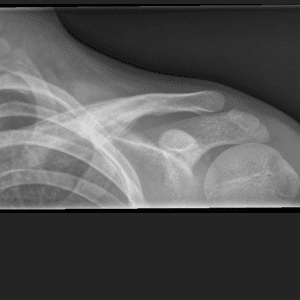

Pediatric Radiographs